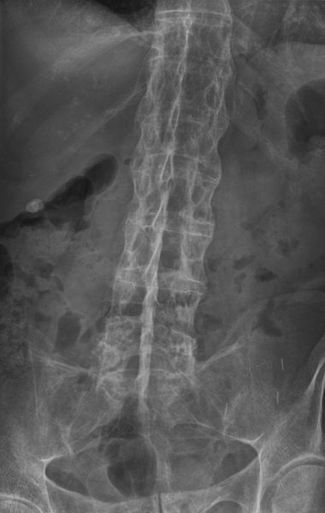

- Look for scoliosis (e.g. in ankylosing spondylitis).

- Check for a question mark posture, commonly seen in ankylosing spondylitis:

- Flattened lumbar lordosis

- Exaggerated thoracic kyphosis

- Cervical hyperextension

- Protruding abdomen (pot belly)

Ankylosing Spondylitis (AS)

- A chronic inflammatory disease affecting the axial skeleton.